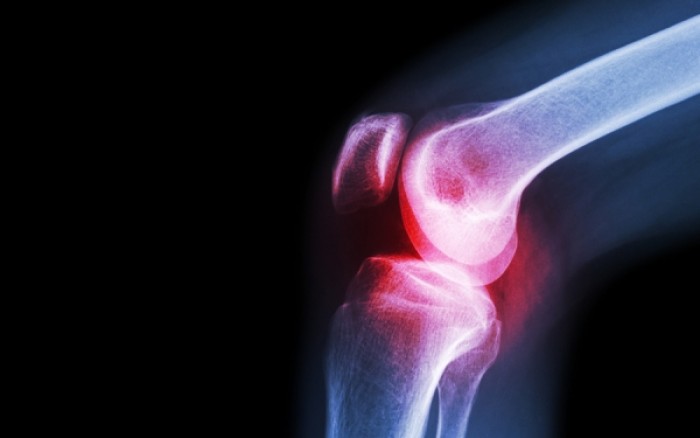

Όταν υπάρχει φλεγμονή στις αρθρώσεις, με αποτέλεσμα αυτές να σκληραίνουν και να πρήζονται, ο πόνος μπορεί να γίνει πραγματικά ανυπόφορος.

Υπολογίζεται ότι 1 στους 5 ενήλικες αντιμετωπίζει κάποια από τις περίπου 100 ιατρικές παθήσεις που επηρεάζουν το μυοσκελετικό σύστημα και ειδικά τις αρθρώσεις, όπου συναντώνται δύο ή περισσότερα οστά.